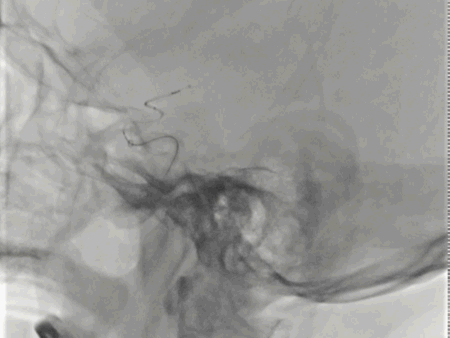

FlowGate 2同轴Catalyst 7、Synchro 2多次调整后穿过C1起始闭塞处,MicroPort Pioneer 2.5mm×20mm球囊C1起始处缓慢扩张,顺球囊Catalyst 7穿过闭塞段,继续向前推进FlowGate 2失败, Catalyst 7 C1抽吸出长条血栓。

Catalyst 7 C1抽吸出大负荷血栓。

Catalyst 7再次通过闭塞处于C2-C4近端抽吸,再无血栓抽出,球囊辅助通过(BTA)技术无法将CAT7带入C4远端,CAT减容任务完成,使用Solitaire FR 6×30支架行完整BADDASS技术, 6×30支架前行张力非常大,释放时并无法顺利推出Rebar 18微导管,导致支架释放略近于预期位置。

支架释放位置不理想,而且前行过程中导致血栓前移,支架并未覆盖血栓头端,经验告诉我们,仅靠软膜支的独立系统可能会通过BGC的血流阻断弥补前向压力(P),远端未覆盖血栓可能会因为血栓之间的粘附力而一并拖出。

充盈FlowGate 2,CAT 7施加张力,希望CAT 7能在支架回撤过程中抓住血栓尾端,但CAT 7在虹吸弯纹丝不动,负压下同时撤出支架与DAC。

BADDASS技术下支架取出长条血栓,3D-DSA可见眼动脉下方重度狭窄,CAT 7在张力下的上行切割狭窄处,导致小夹层产生。